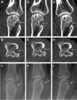

Gouty erosion

Gout is a form of inflammatory arthritis characterized by recurrent attacks of a red, tender, hot, and swollen joint. Pain typically comes on rapidly, reaching maximal intensity in less than 12 hours. [Source: Wikipedia ]